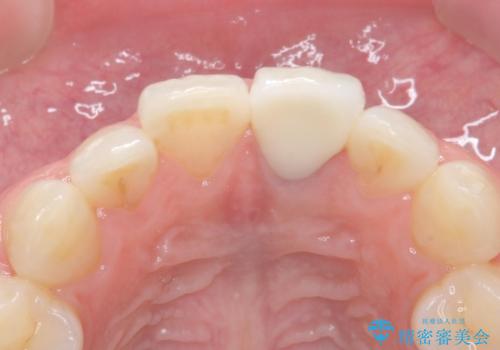

前歯が暗く変色 ジルコニアクラウンでの修復

- 前歯の変色を主訴に来院された患者様です。

より審美的な修復を行いたいとのことであったため、ジルコニアクラウンでの修復を行います。

周囲の歯との色調に調和した審美的なクラウンを装着することができました。

歯茎の状態も良く、とても良い仕上がりになりました。